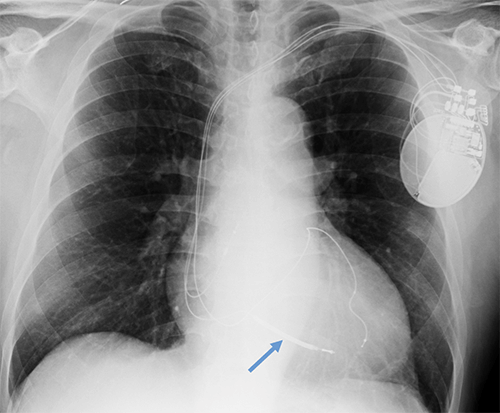

- CEID images with lead types:

Pacemaker with transvenous leads

Pacemaker with epicardial leads

Defibrillator lead

Subcutaneous defibrillator

Cut epicardial wires (often hard to see)

Abandoned leads

Abanded leads plus generator

Temporary transvenous lead

Leadless pacemaker

Abandoned, in situ intracardiac and epicardial leads